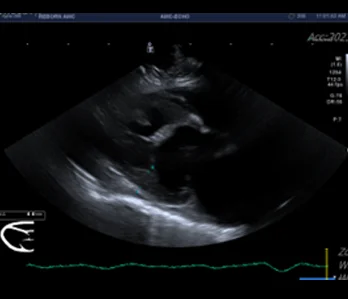

• 초음파

영상의학과는 X-ray, 초음파, CT, MRI 등 다양한 첨단 장비를 활용하여 동물의 내부 상태를 영상으로 표현하고, 이를 기반으로 정확한 진단과 치료 방향을 제시하는 역할을 합니다.

• 초음파 케이스 수 : 3만 7천건 이상